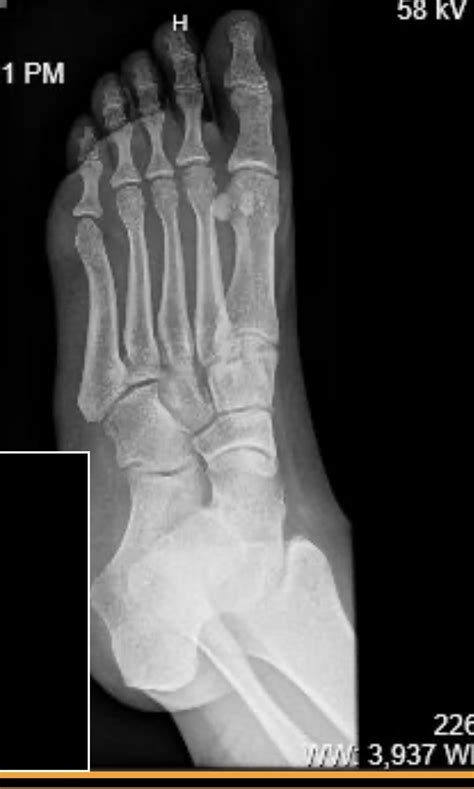

Diagnosing a Hairline Fracture in the Foot

Diagnosing a hairline fracture in the foot typically involves a combination of physical examination and imaging tests. The diagnostic process may include:

• Imaging Tests: X-rays, MRI, or bone scans may be ordered to visualize the fracture and confirm the diagnosis.

X-rays are often the first line of imaging, but they may not always detect hairline fractures, especially in the early stages. In such cases, an MRI or bone scan may be necessary to provide a more detailed view of the bone structure.